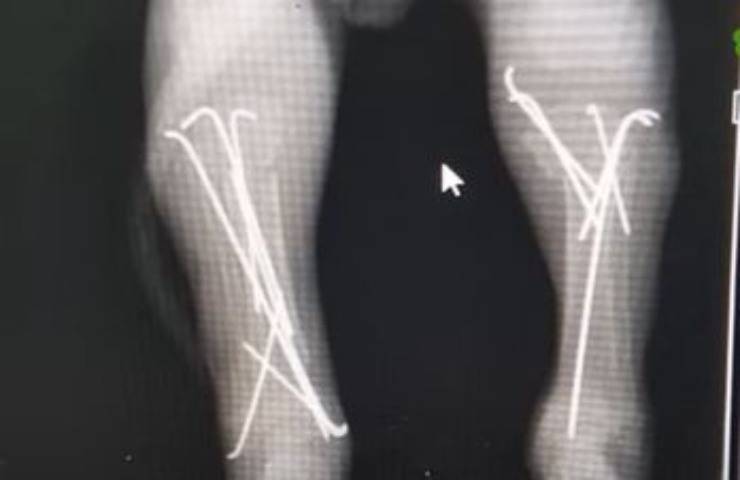

Il cucciolo infatti oltre ad avere le zampe rotte in tre punti diversi aveva anche un’ernia, mentre la colonna vertebrale fortunatamente nonostante i maltrattamenti era rimasta intatta.

Il piccolo è stato portato immediatamente presso un centro veterinario dove o medici hanno deciso di procedere con un intervento chirurgico per cercare di salvargli le zampe .

Contro ogni aspettativa dopo l’intervento dopo soli sette giorni, Gabi si è alzato ed ha iniziato a muovere i primi timidi passi sulle zampe che erano state date per spacciate